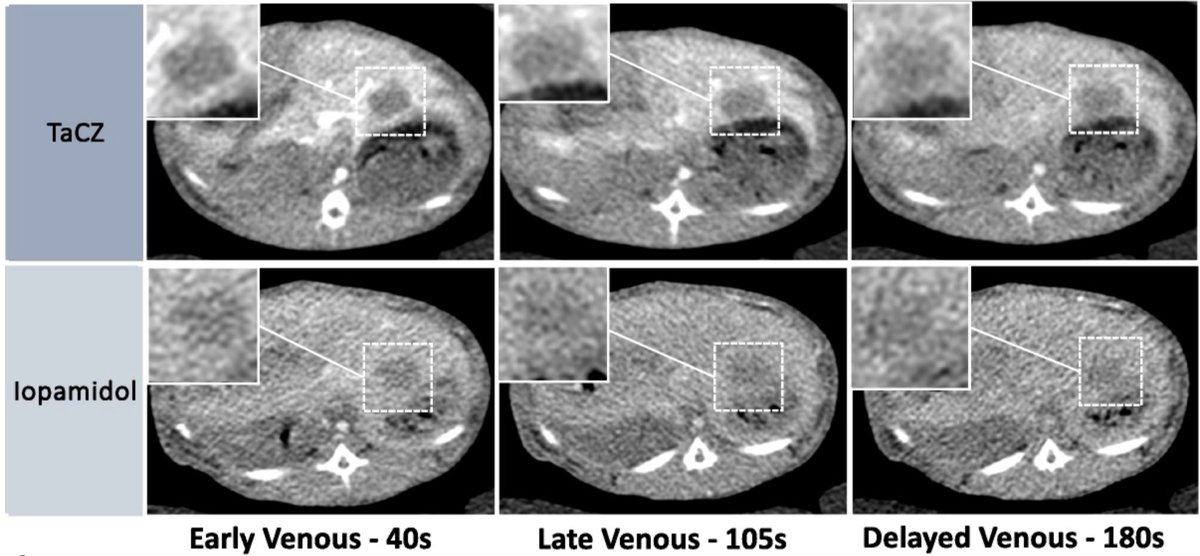

Heimer et al. demonstrate in a preclinical study that a #TantalumOxide–based nanoparticle #ContrastAgent showed higher hepatic contrast enhancement and improved the detection of #HepaticTumors in #ComputedTomography. UCSF Imaging #LMUradiology doi.org/10.1097/rli.00…

Heimer et al. demonstrate in a preclinical study that a #TantalumOxide–based nanoparticle #ContrastAgent showed higher hepatic contrast enhancement and improved the detection of #HepaticTumors in #ComputedTomography. <a href="/UCSFimaging/">UCSF Imaging</a> #LMUradiology

doi.org/10.1097/rli.00…